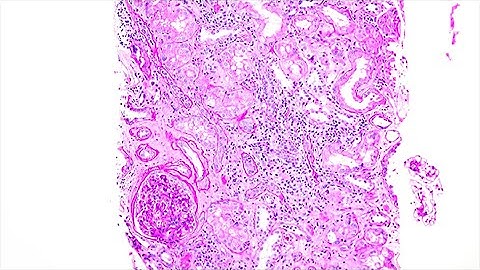

Unravelling the Complex Landscape of Cellular Rejection Are we there yet? Insights from Single Cell